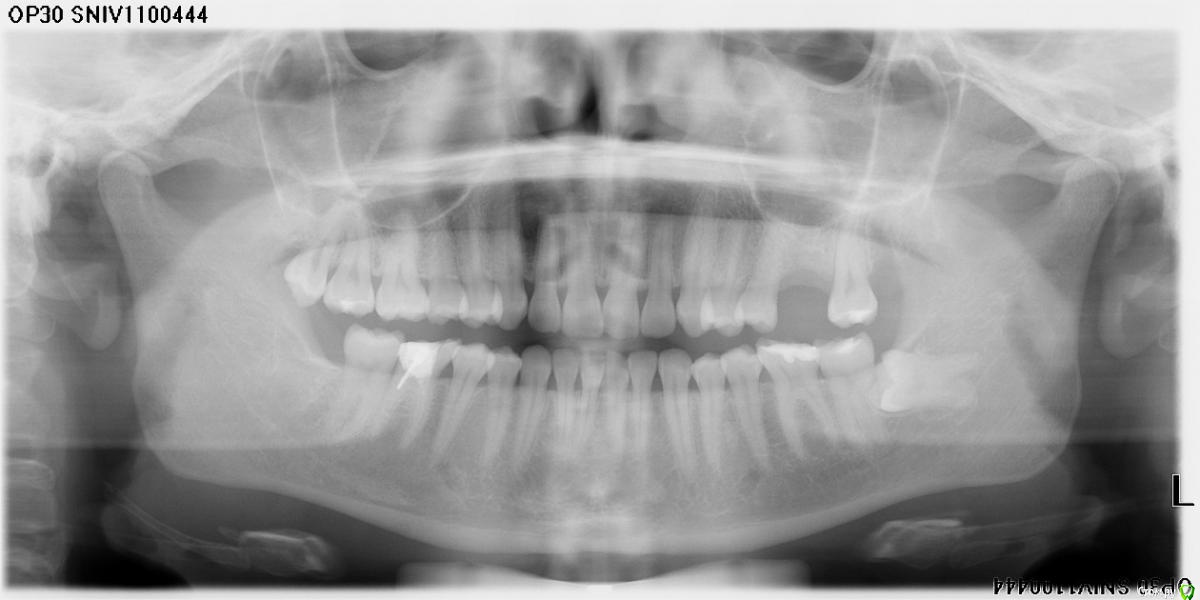

Kuksvi_86@mail.ru Опубликовано 28 ноября, 2019 Поделиться Опубликовано 28 ноября, 2019 (изменено) Здравствуйте, сегодня была на сложном удалении 8 зуба слева, 3 часа со мной возились, 2 раза кололи обезбол, артикаин и лидокаин. Мне было очень больно, когда особенно стали трогать корни боль дичайшая.Время затягиваплось, я поняла, что не вывезу этого ужаса.Да и они ковырялись и не могли ничего удалить, бесконечная пилежка, элеватором раскачка. Пожалела миллион раз, что согласилась, лучше бы ходила с кривыми зубами. До этого правую нижнюю мне удаляли(она была чуть чуть прорезана) и верхние два зуба тоже. Было неприятно, тяжело, но я пережила. Мне выписали направление на общий наркоз. Боюсь до ужаса наркоз, не понимаю почему так больно было. Ещё вопрос, если не удалять, то что будет? Какие осложнения? Они будут сами выходить? Пью линкомицин, найс. Уже не хочу ничего удалять настолько все было ужасающе. Расскажите, пожалуйста, о последствиях, если оставлю, почему так больно? Не сломали ли мне вообще челюсть? Могут ли сломать если пойду на общий наркоз? Выйдут ли зубы сами, через сколько времени надо идти на операцию? Я так поняла врач слабый, хоть и бабушка какая то. Прокомментируйте, пожалуйста, мою ситуацию. Пожалуйста, без насмешек и цинизма, сарказма, спасибо. Очень жду. За ошибки простите, с телефона пишуЗдравствуйте, сегодня была на сложном удалении 8 зуба слева, 3 часа со мной возились, 2 раза кололи обезбол, артикаин и лидокаин. Мне было очень больно, когда особенно стали трогать корни боль дичайшая.Время затягиваплось, я поняла, что не вывезу этого ужаса.Да и они ковырялись и не могли ничего удалить, бесконечная пилежка, элеватором раскачка. Пожалела миллион раз, что согласилась, лучше бы ходила с кривыми зубами. До этого правую нижнюю мне удаляли(она была чуть чуть прорезана) и верхние два зуба тоже. Было неприятно, тяжело, но я пережила. Мне выписали направление на общий наркоз. Боюсь до ужаса наркоз, не понимаю почему так больно было. Ещё вопрос, если не удалять, то что будет? Какие осложнения? Они будут сами выходить? Пью линкомицин, найс. Уже не хочу ничего удалять настолько все было ужасающе. Расскажите, пожалуйста, о последствиях, если оставлю, почему так больно? Не сломали ли мне вообще челюсть? Могут ли сломать если пойду на общий наркоз? Выйдут ли зубы сами, через сколько времени надо идти на операцию? Я так поняла врач слабый, хоть и бабушка какая то. Прокомментируйте, пожалуйста, мою ситуацию. Пожалуйста, без насмешек и цинизма, сарказма, спасибо. Очень жду. За ошибки простите, с телефона пишу Изменено 28 ноября, 2019 пользователем Kuksvi_86@mail.ru 1 1 Ссылка на комментарий

Jurai Опубликовано 28 ноября, 2019 Поделиться Опубликовано 28 ноября, 2019 Удаляли в поликлинике? С анестезией не повезло, поэтому не подействовала на вас. Челюсть не сломали, зуб нужно удалить полностью. Не самый простой, конечно зуб, но и не ужасный. Сделайте компьютерную томографию этого участка, не тяните - возникнет отек, рот будет плохо открываться. И попробуйте найти хирурга, который возьмется, или обратиться в отделение челюстно-лицевой хирургии. 1 Ссылка на комментарий